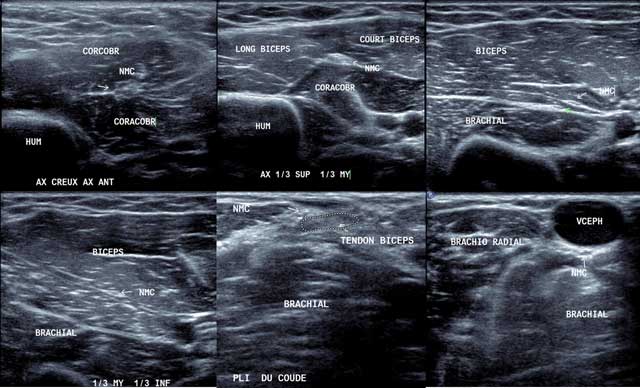

Figure 15

Pectoralis Major tendon on the humerus. Chef Sternal: sternal muscle, Chef Claviculaire: Clavicular muscle, Chef Costo Abdominal: Costo-abdominal muscle, Coulisse Bicipitale: Bicipital area.

Figure 16

Axial view of the normal anterior part of the humerus in external position (a) with hydroxyapatite deposits in X-rays (b) and US in sagittal and axial view (d). GRD/GDO: Teres Major/Latissimus Dorsi, GRD PECT: Pectoralis Major, HUM: Humerus, Court Biceps: Short head of the biceps.